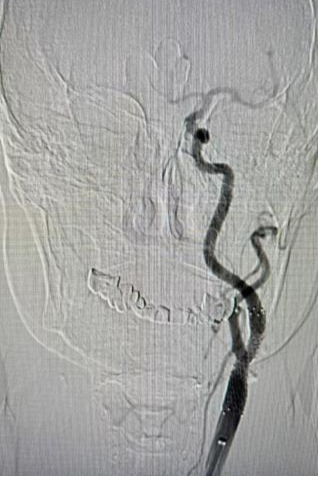

手术当日,血管外科主任汪岩及副主任医师李晓亮凭借丰富的经验与精湛的技术,经股动脉穿刺建立通道。在脑保护装置全程防护下,先使用球囊扩张狭窄部位,随后精准地将支架送至狭窄处并释放,成功撑开闭塞血管,恢复脑部血流灌注。整个手术过程仅留下微小创口,无需全麻开颈。术中,医护人员严密监测患者生命体征变化,确保手术顺利完成。术后造影显示,血管通畅,支架贴壁良好。

▲手术后